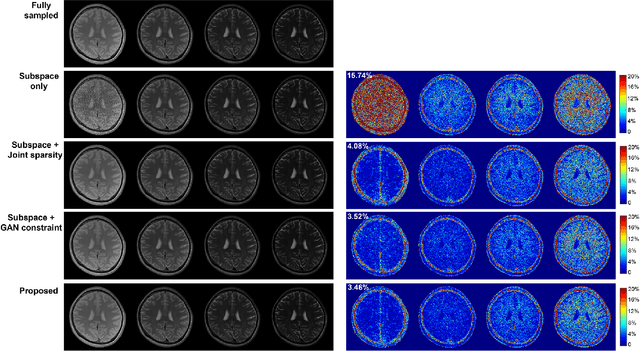

Abstract:We present a novel method that integrates subspace modeling with an adaptive generative image prior for high-dimensional MR image reconstruction. The subspace model imposes an explicit low-dimensional representation of the high-dimensional images, while the generative image prior serves as a spatial constraint on the "contrast-weighted" images or the spatial coefficients of the subspace model. A formulation was introduced to synergize these two components with complimentary regularization such as joint sparsity. A special pretraining plus subject-specific network adaptation strategy was proposed to construct an accurate generative-model-based representation for images with varying contrasts, validated by experimental data. An iterative algorithm was introduced to jointly update the subspace coefficients and the multiresolution latent space of the generative image model that leveraged a recently developed intermediate layer optimization technique for network inversion. We evaluated the utility of the proposed method in two high-dimensional imaging applications: accelerated MR parameter mapping and high-resolution MRSI. Improved performance over state-of-the-art subspace-based methods was demonstrated in both cases. Our work demonstrated the potential of integrating data-driven and adaptive generative models with low-dimensional representation for high-dimensional imaging problems.